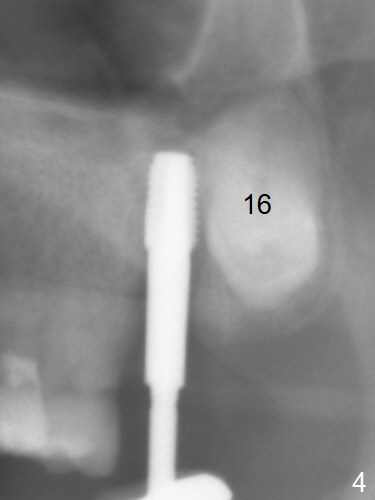

Extraction of the tooth #15 with short clinical crown (suggesting bruxism, Fig.1) reveals a vertical root fracture (Fig.2 <). It seems unnecessary and difficult to create osteotomy in the mesial slope. What can be done is to place starter and 2 mm drills as mesial as possible (Fig.3 (red dashed line: sinus floor). After use of Lindamann bur to move the osteotomy mesially and sequential osteotomy until 3.8x18 mm, a 4.5 mm tap is inserted with clearance from the impacted tooth #16 (Fig.4). A 5x15 mm implant is placed with >60 Ncm with clearance from the 3rd molar (Fig.5,6). If the impacted tooth were removed, the primary stability is expected to be reduced. Impression is taken 6 months postop with 19/20 implants (Fig.7). The bone graft remains in the crestal area immediately and 11 months post cementation (Fig.8,9 *). In the other word, new crestal bone forms after extraction.